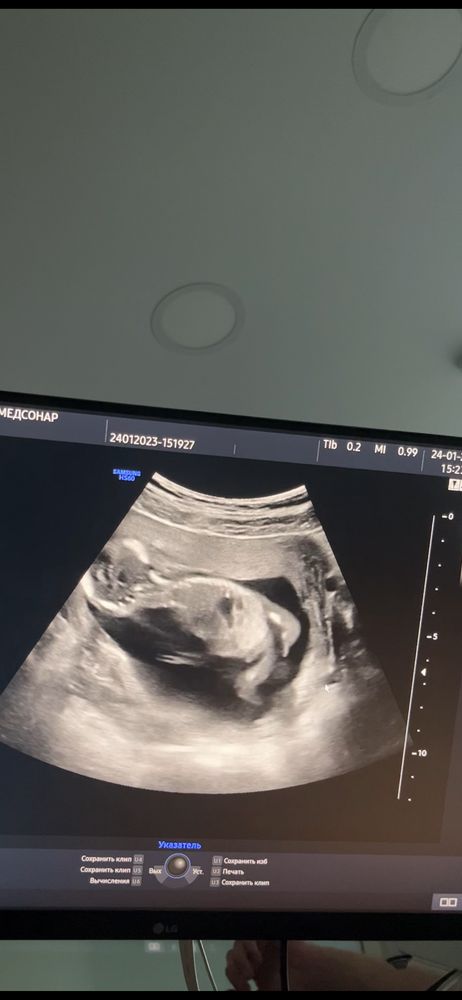

Вы больше девочку видите или мальчика?

А узист-то что сказал? На 27 неделе там все прекрасно видно.

Ray, сказал вроде девочка,прячется человек🥰

Ничего не торчит,девочка

Девочка у вас.

не специалист, но писюна не вижу))

На мальчика больше похоже (я не про бородатого 😅)

Девочка вроде, у нас в 13 недель кажется такой же вид

Мальчик явно